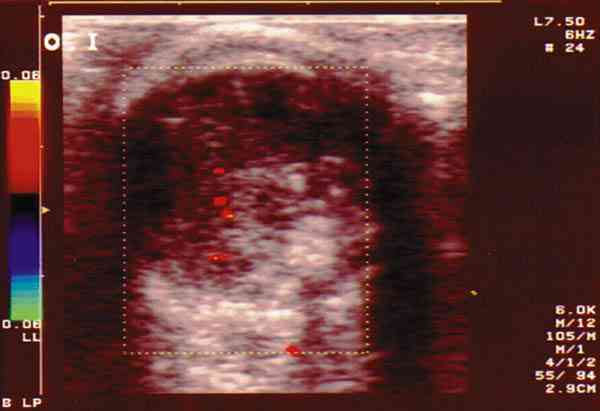

Figura 6. RB con extensa calcificación. Doppler color: registro

arterial en área no calcificada.